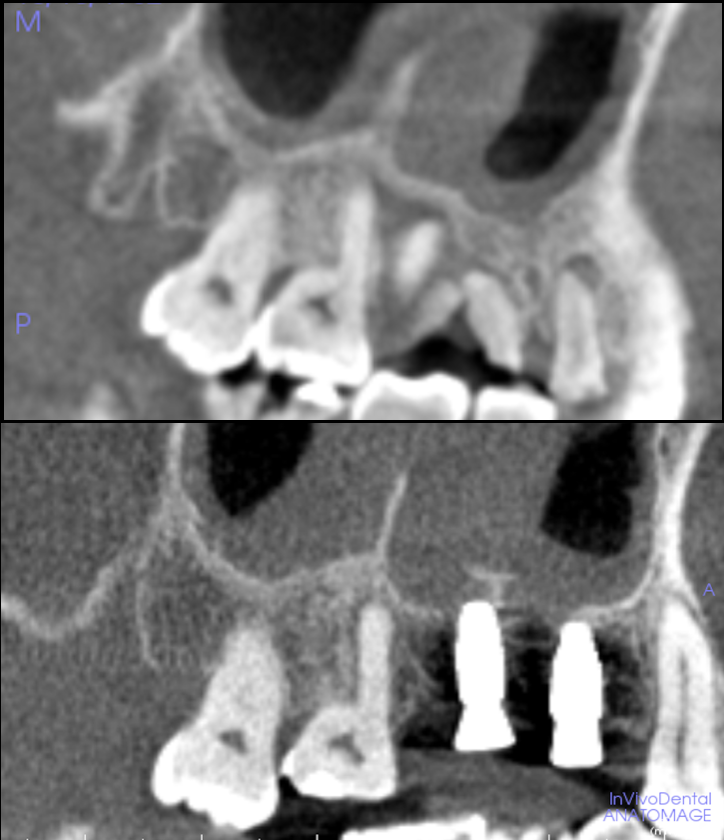

[池袋 歯医者]サイナスリフトを回避できる?低侵...

[池袋 歯医者]歯の移植〜インプラントをする前に...

【グランドメゾンデンタルクリニック】抜歯後の骨...